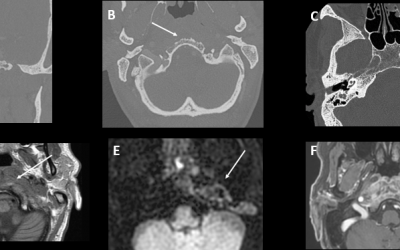

Caso del mes Febrero 2026

« Todos los casosAutores Victoria Esteban Izquierdo Enrique Marco de Lucas Hospital Universitario...